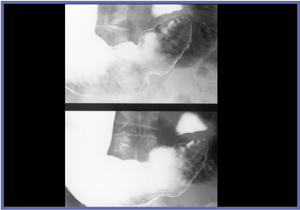

精度向上に直接つながる熟練した撮影技術の会得には,日常的にびらんを撮影することが有効である。びらんは,アレアとともに胃の凹凸の中では最小サイズであるため,これを意識的に撮影することが日々の訓練となる。がんは,日常的にはほとんど遭遇しない(発見率0.3%程度)が,びらんの所見は18%程度ある。当院のびらん所見を調べたところ,形状はたこいぼびらんが80%を占め,占拠部位は83%が前庭部に集中していた。前庭部前壁二重造影,前庭部空気少量二重造影,圧迫,後壁二重造影などでびらんを撮影することが,技術向上に有効であろう。前庭部のバリウムと空気が入れ替わる一瞬のびらん撮影(図7),ていねいに圧迫してびらんをびらんらしくとらえる(図8)など,びらん撮影はテクニックを磨く上で重要である。

![]() 図7 前庭部空気少量二重造影 |

![]() 図8 圧迫撮影 |